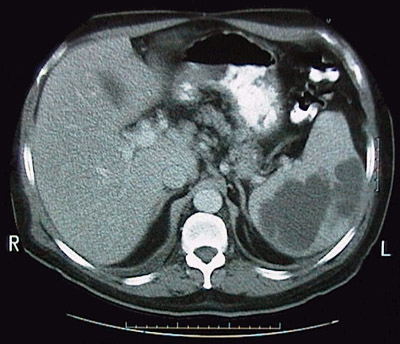

Click on the abscesses in spleen in the CT scan above:

Large lucent abscesses of the enlarged spleen are demonstrated here. These most often occur in the setting of septic embolization.